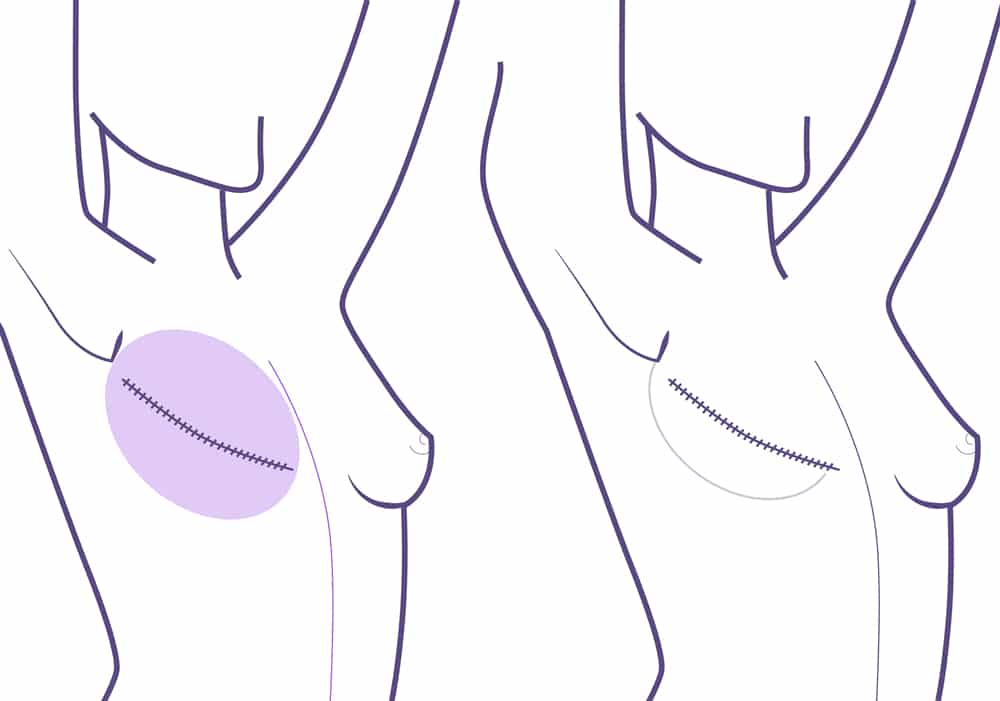

Si es seguro desde el punto de vista oncológico, se pueden conservar areola y pezón. En los casos en los que esto no es posible se reconstruyen después, mediante anestesia local y de manera ambulatoria, o mediante micropigmentación.

Hoy en día, gracias a los avances médicos, son cada vez más los casos en los que se puede hacer una mastectomía ahorradora de areola y pezón. En los casos en los que oncológicamente esto no es seguro y precisan la retirada del complejo areola-pezón, la reconstrucción habitualmente ha de demorarse. Se realiza con anestesia local y de manera ambulatoria en un segundo tiempo, e incluso puede tatuarse.